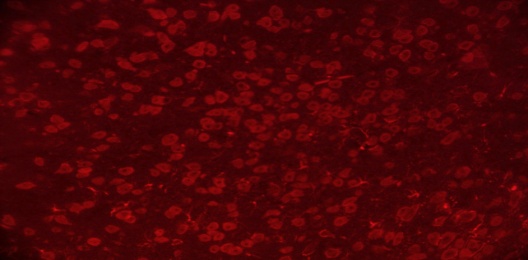

TEL increased NeuN expressions in MPTP intoxicated mice brain

SNpc and ST regions of MPTP mice brain showed a significant decrease in % NeuN immunopositive cells [F (4,10) = 274.1, p<0.01 and F (4,10) = 86.24, p<0.01, respectively] when compared to the vehicle treated mice. TEL (3 and 10 mg/kg) significantly (p<0.01) increased % NeuN immunopositive cells in both the regions in comparison to MPTP mice (fig. 4).

Fig. 4: Effect of TEL on % NeuN immunopositive cells in MPTP intoxicated mice brain. Pictures represent NeuN immunopositive cells of (A) SNPc and (B) ST brain regions X 400 magnification. (1) Normal control, (2) MPTP induced mice brain, (3) TEL (3 mg/kg b. wt.) administered MPTP mice brain, (4) TEL (10 mg/kg b. wt.) administered MPTP mice brain and (5) TEL (10 mg/kg b. wt.) administered normal mice brain. (C) Values were expressed in mean±SEM, n=4 animals/group, statistical analysis was performed using one way ANOVA followed by Tukey’s multiple comparison test, ## indicates p value<0.01 Vs group I, ** indicates p value<0.01 Vs group II